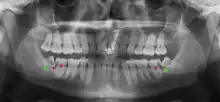

Impacted wisdom teeth are classified by their direction of impaction, their depth compared to the biting surface of adjacent teeth and the amount of the tooth's crown that extends through gum tissue or bone. Impacted wisdom teeth can also be classified by the presence or absence of symptoms and disease. Screening for the presence of wisdom teeth often begins in late adolescence when a partially developed tooth may become impacted. Screening commonly includes a clinical examination as well as x-rays such as panoramic radiographs.

If the tooth cannot be assessed with clinical exam alone, the diagnosis is made using either a panoramic radiograph or cone-beam CT. Where unerupted wisdom teeth still have eruption potential several predictors are used to determine the chance of the teeth becoming impacted. The ratio of space between the tooth crown length and the amount of space available, the angle of the teeth compared to the other teeth are the two most commonly used predictors, with the space ratio being the most accurate. Despite the capacity for movement into early adulthood, the likelihood that the tooth will become impacted can be predicted when the ratio of space available to the length of the crown of the tooth is under 1.[5]: 141

There is no standard to screen for wisdom teeth. It has been suggested, absent evidence to support routinely retaining or removing wisdom teeth, that evaluation with panoramic radiograph, starting between the ages of 16 and 25 be completed every 3 years. Once there is the possibility of the teeth developing disease, then a discussion about the operative risks versus long-term risk of retention with an oral and maxillofacial surgeon or other clinician trained to evaluate wisdom teeth is recommended. These recommendations are based on expert opinion level evidence.[19] Screening at a younger age may be required if the second molars (the "12-year molars") fail to erupt as ectopic positioning of the wisdom teeth can prevent their eruption. Radiographs can be avoided if the majority of the tooth is visible in the mouth.